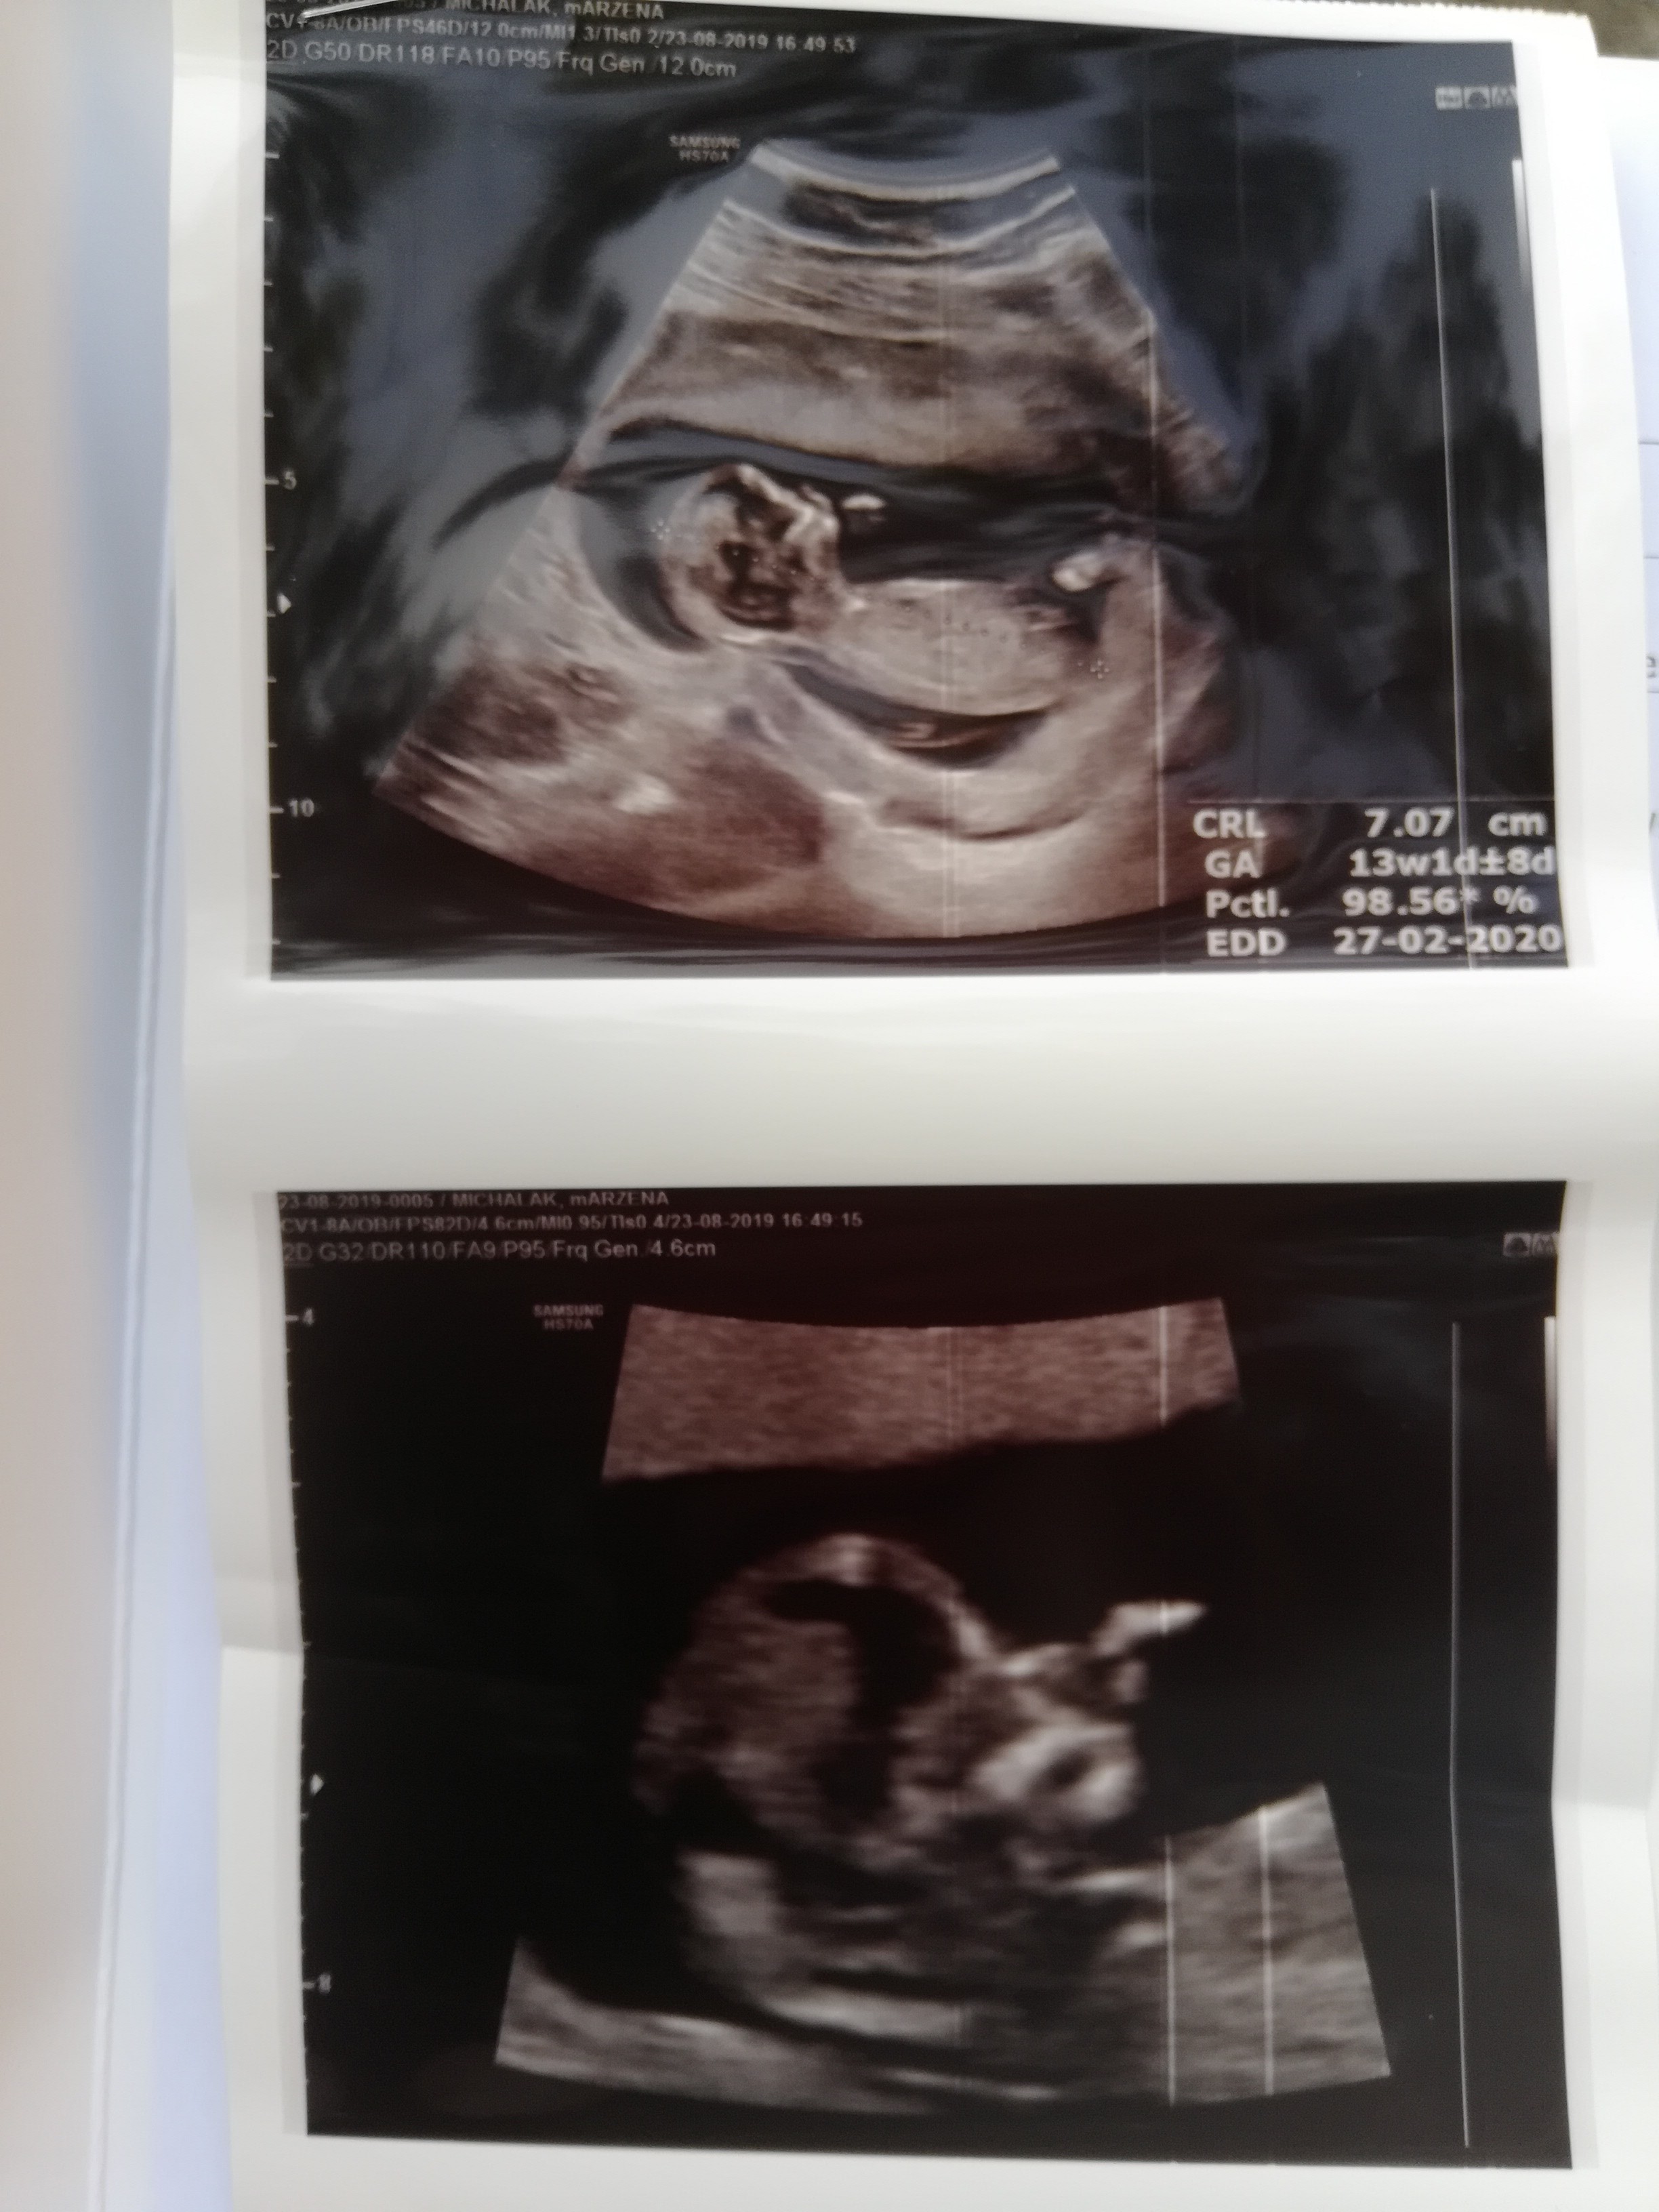

Hej byłam teraz na usg prenatalnym i jest wszystko ok, chociaż ryzyko nie jest takie duże jak u innych. U mnie trisomia 21 to 1:1304, trisomia 18 to 1:3223 i trisomia 13 <1:20000. Przeziernosc wychodzi 2,1 mm. Serduszko 162 i długości 7,07 cm. Ogolnie lekarz się skłania w kierunku chłopca i bardzo bym tego chciała żeby tak było.